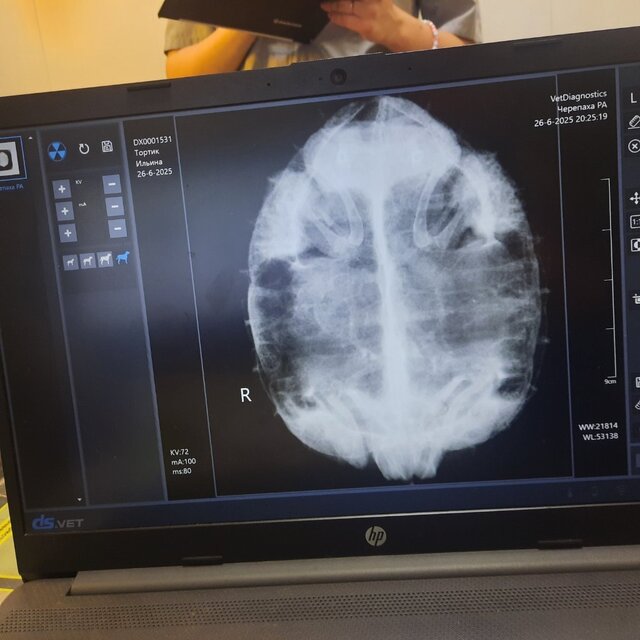

Всем добрый день, задам тут вопросы по лечению черепахи, потому что у нас в городе, видимо нет хороших герпетологов. Мы обратились в клинику с подозрениями на пневмонию (вина моя, вовремя грелку для воды не купила). Рентген снимок будет ниже. Нам назначили Энроксил 5% в дозе 0,04 в/м 10 дней. Я ставила всегда только в одну переднюю конечность( мышцу), не чередовала, сейчас заметила что черепаха стала в воде заваливаться именно на ту сторону, в которую ставили укол. У меня вопрос, мне нужно было чередовать стороны?

в этой проекции лёгкие не видно и поставить диагноз пневмония и вообще оценить лёгкие по нему невозможно. Антибиотик вам тоже назначили неправильную дозировку, в 2 раза ниже нужной, что плохо, если там действительно пневмония.

вам нужно будет переделать рентген в правильных проекциях и уже на основе результата врач вам подберёт препарат, т.к. предыдущий вам назначили в маленькой дозировке.